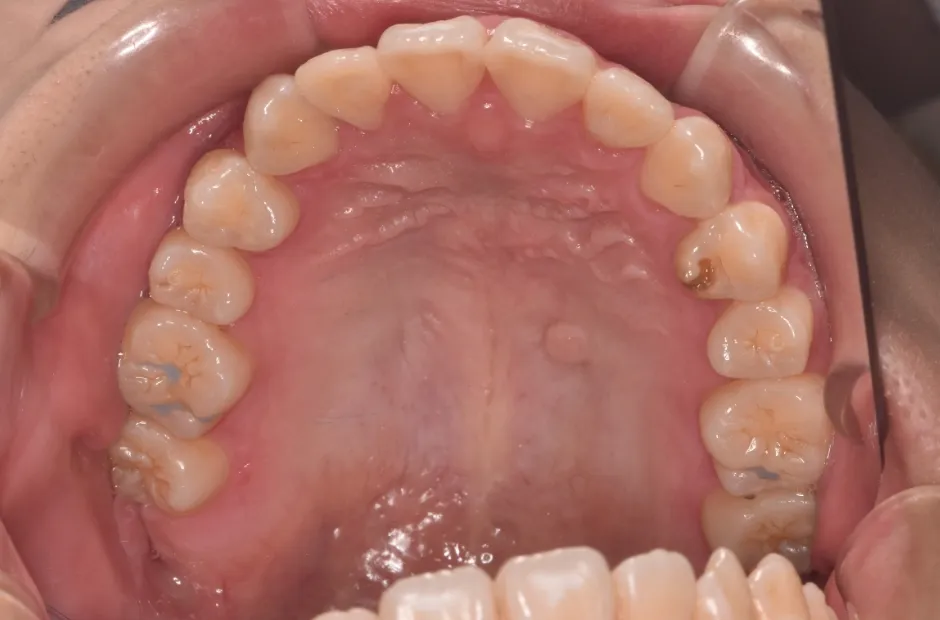

叢生

| 診断名・主訴 | 叢生 |

|---|---|

| 年齢・性別 | 43歳・女性 |

| 治療期間・回数 | 2年7か月 27回 |

| 治療に用いた主な装置 | 舌側矯正 |

| 抜歯部位 | 両顎4,4 |

| 治療費 | 100万円(税抜) |

| リスク・副作用 | 装置による違和感・疼痛・歯肉退縮・歯根吸収・虫歯のリスクなど |

治療前